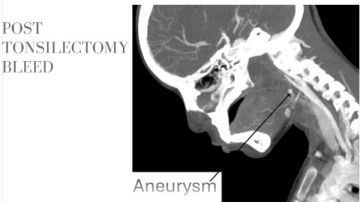

وأضاف أن فريق الأشعة التداخلية أجرى الفحوصات والأشعات اللازمة فور وصول الطفلة، والتي كشفت عن وجود تمدد شرياني نازف بأحد الشرايين الرئيسية بالرقبة في جدار الحلق، ما تطلب تدخلاً عاجلاً عالي الدقة.

ومن جانبه، ذكر الدكتور احمد كمال المدير التنفيذي للمستشفيات الجامعية، أنه تم تجهيز وحدة القسطرة على الفور، حيث نجح الفريق الطبي في غلق التمدد الشرياني باستخدام حلزونات دقيقة عبر القسطرة التداخلية.

مما أسهم في السيطرة الكاملة على النزيف دون الحاجة إلى جراحة تقليدية، وتقليل احتمالات المضاعفات.